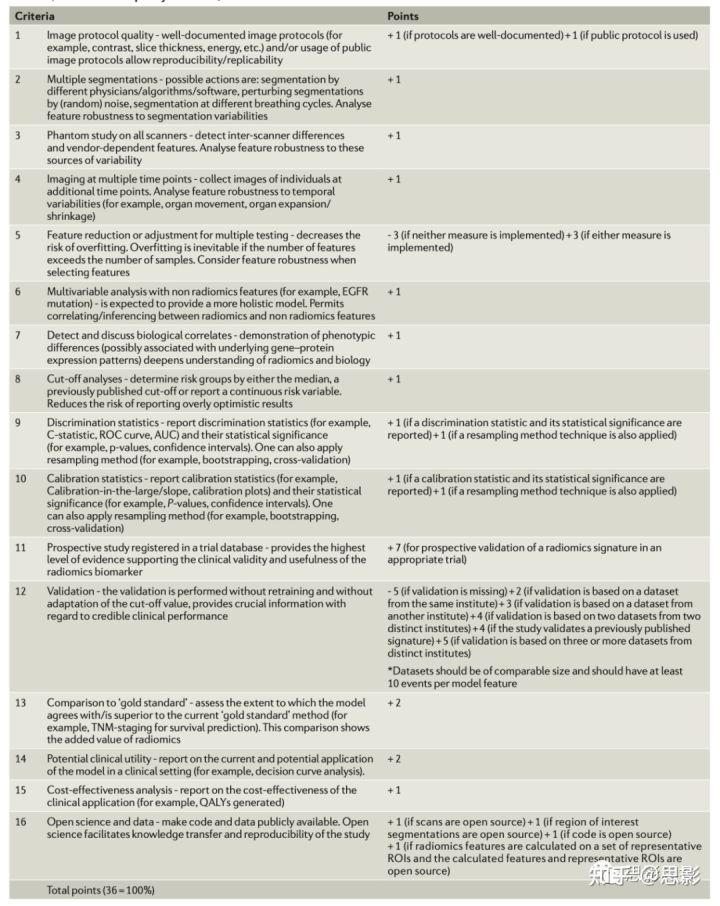

影像组学质量评分

随着影像组学的发展,迫切需要同质的评估标准和报告指南,以使影像医学发展成为一个领域。我们提出了影像组学质量评分(RQS),以帮助评估过去和未来的影像组学研究。

编辑、评审员和读者应该能够确定一项影像研究是否符合最佳实践程序,或者研究人员是否有充分理由证明不符合指南。出版物应明确说明该研究如何通过明确需求来推进影像医学领域。关于鲁棒性和普遍性的过于乐观的说法会削弱科学和临床影响,应该避免。研究期刊应广泛报告研究设计、方案、详细的质量保证过程和标准操作程序。尽管影像组学的细微技术的细节令人乏味,但它们可以极大地影响稳健性、普遍性和混淆meta分析。严格的报告指南对于影像组学方法的成熟是必要的。

RQS(影像组学质量评分)的标准

大量证据表明,预测模型研究的研究报告质量目前很差。预测模型的各个方面都需要完整、清晰的报告,以最大限度地减少偏差,提高预测模型的实用性。一个很好的例子是个体预后或诊断多变量预测模型(TRIPOD)倡议的公开报告。在该倡议中,建立了一套建议,用于报告开发、验证或更新预测模型的研究,无论该模型是否用于诊断或预测目的。我们在特定于影像组学的背景下模拟了这种方法,并建议应通过RQS对研究进行评估,为此我们确定了16个关键组成部分;根据表1中详细说明的各个部分的重要性,每个环节都分配了若干点。